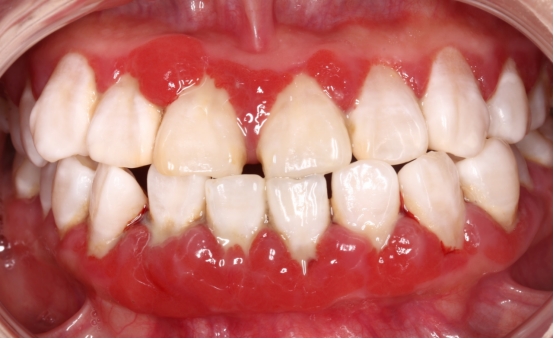

牙龈出血

刷牙出血是牙龈炎症最早且最容易发现的症状,也是牙周组织最先发出的危险警告。如果使用一些含止血成分的药用牙膏,这种牙龈炎症的“报警”就会被掩盖,导致牙周炎症继续进展,进而造成牙槽骨的炎症。